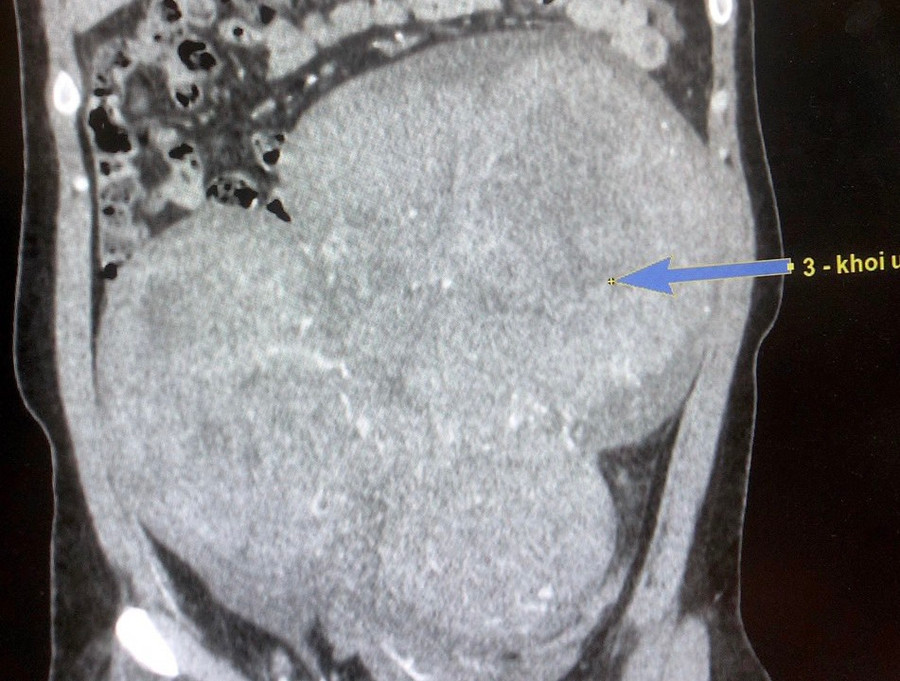

Kết quả siêu âm, chụp cắt lớp vi tính có tiêm thuốc cản quang ghi nhận u to vùng ổ bụng xuất phát từ vùng hạ vị, kích thước khoảng 12 x 25 x 28 cm có tăng sinh mạch máu.

| Hình ảnh chụp cắt lớp vi tính ghi nhận bệnh nhân có u to vùng ổ bụng xuất phát từ vùng hạ vị. Ảnh: Đình Tuyển |